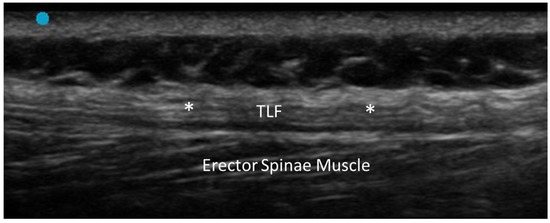

- Pirri, C.; Pirri, N.; Guidolin, D.; Macchi, V.; Porzionato, A.; De Caro, R.; Stecco, C. Ultrasound Imaging of Thoracolumbar Fascia Thickness: Chronic Non-Specific Lower Back Pain versus Healthy Subjects; A Sign of a “Frozen Back”? Diagnostics 2023, 13, 1436. [Google Scholar] [CrossRef] [PubMed] [PubMed Central]